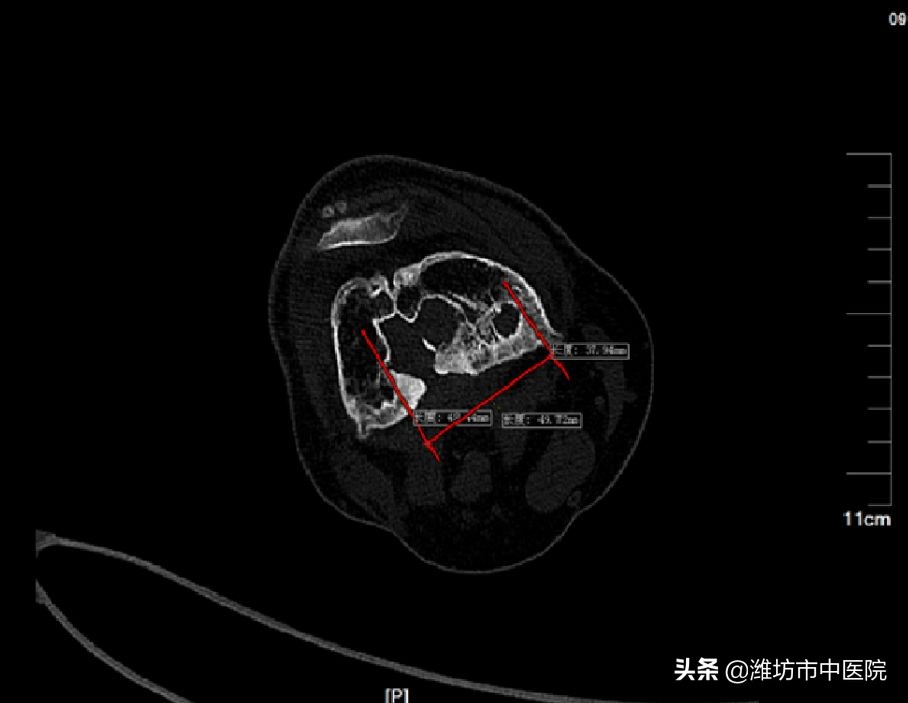

老人的股骨骨髓炎已有50多年,极为少见,股骨大量被侵蚀、破坏,死骨大量形成,范围占据大腿长度的2/3,达到了罕见的25cm,远端部分已经接近膝关节,既要清除病灶,又要保护膝关节,还要保证股骨的强度,避免骨折,治疗起来难度极大,对专业程度要求极高。患者入院后,张荣峰主任仔细研究影像学资料,准确判断感染病灶的范围,结合上千例骨髓炎的治疗经验,为患者制定了个体化的精准治疗方案,并且融入近几年骨感染治疗的先进理念和技术。经充分准备,在冯云华主任的大力支持下,在手术室人员的密切协作下,于10月4日进行了手术治疗。虽然手术过程繁琐、复杂,但是手术极其顺利、术中出血很少。